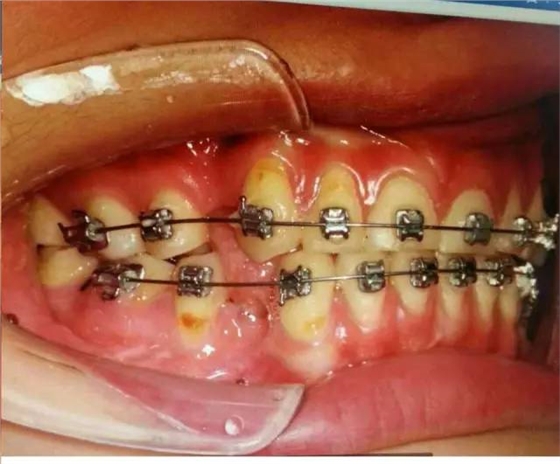

中醫(yī)有云“未病先防”,權(quán)老師發(fā)現(xiàn)患者舌位置的異常,檢查患者的吞咽方式,驗證其為嬰兒式吞咽。而舌在嬰兒式吞咽甚至是整個口頜系統(tǒng)中的作用是不可小覷的。嬰兒式吞咽舌頭抵在下牙,吞咽時會對牙齒產(chǎn)生向外的推力,應(yīng)力集中在頸部,導(dǎo)致牙齒微折裂,甚至出現(xiàn)牙齦萎縮、楔缺、牙根暴露,引起牙的冷熱痛。臨床上會發(fā)現(xiàn)一些前牙開(牙合)的病人前牙依然受到創(chuàng)傷,沒錯,依然是舌頭惹的禍。這也可以推測照片中患者13,43,45牙齦萎縮和頸部楔狀缺損與舌有關(guān)。

由此,我們可以總結(jié)得出: 患者牙齒出現(xiàn)的癥狀是矯治,側(cè)方干擾,以及舌的推力等因素疊加所致